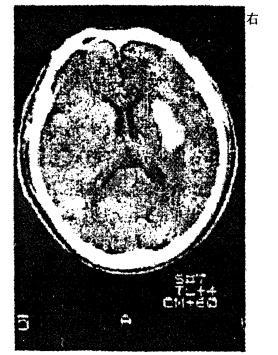

问题 男性,56岁。高血压患者。旅游登山中突然左侧 肢体发麻、乏力。急送医院,摄头颅CT片如图 最可能的诊断是 A.脑出血 B.脑血栓形成 C.蛛网膜下腔出血 D.脑栓塞 E.短暂脑缺血发作

答案 A